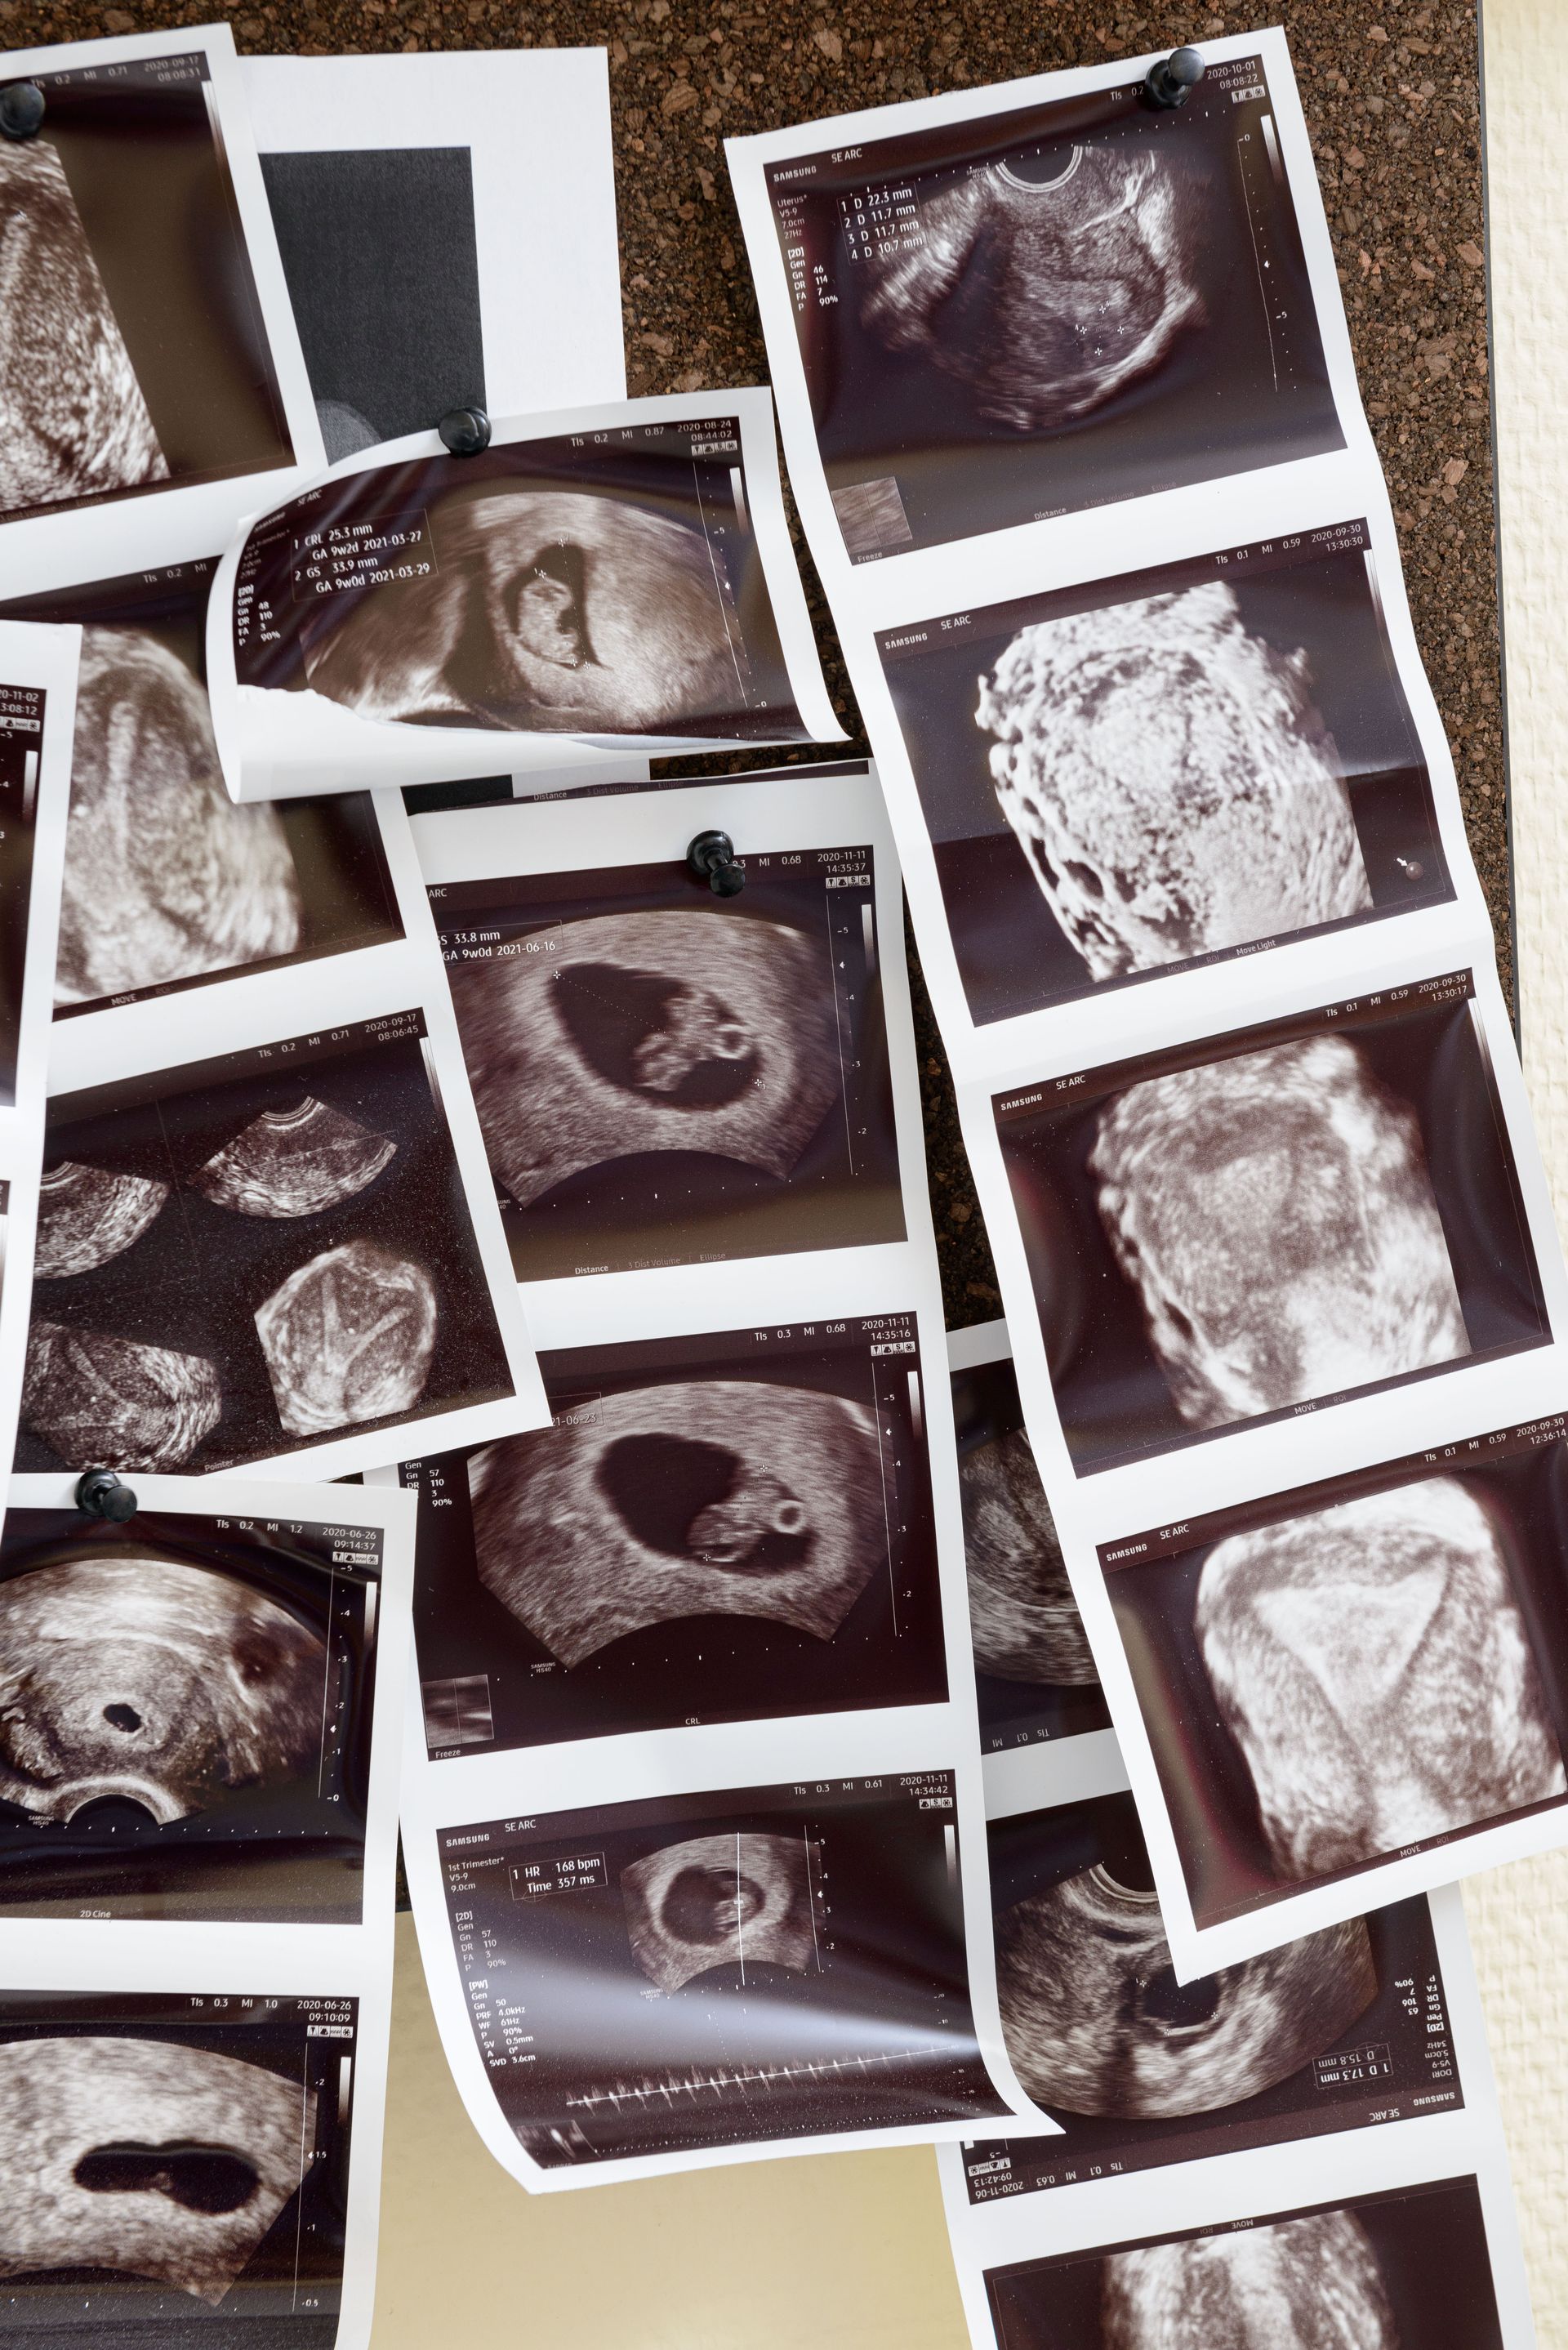

Az iránymutatás részletes klinikai ellátási útvonalat vázol fel. A folyamat az első konzultációval indul, amely során részletes kórelőzmény-felvétel és fizikális vizsgálat történik. Ezt követik a célzott női és férfi reproduktív vizsgálatok, a társbetegségek feltérképezése, majd a diagnózis felállítása és a kezelési terv kidolgozása.

A strukturált megközelítés célja az egységes, magas színvonalú ellátás biztosítása világszerte, függetlenül attól, hogy a beteg melyik ország egészségügyi rendszerében kap ellátást.